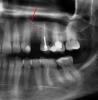

kriokov Опубликовано 22 ноября, 2012 Поделиться Опубликовано 22 ноября, 2012 10 мм легко войдет, коллеги, вам, что по орто не видно? Там 11.5 бикортикально встанет.хорошо вижу только только эту границу, обьясните пожалуйста если не прав Ссылка на комментарий

Bier Опубликовано 23 ноября, 2012 Поделиться Опубликовано 23 ноября, 2012 Ну так ярко белая полоса и есть граница пазухи. На орто всегда искажения, но искажения же не локальные... Я ориентируюсь на размеры зубов. Потом по кт тоже самое получается. 10 мм тут можно спокойно ставить. 1 Ссылка на комментарий

kriokov Опубликовано 23 ноября, 2012 Поделиться Опубликовано 23 ноября, 2012 Ну так ярко белая полоса и есть граница пазухи. На орто всегда искажения, но искажения же не локальные... Я ориентируюсь на размеры зубов. Потом по кт тоже самое получается. 10 мм тут можно спокойно ставить.удален 24, там чудеса бывают с границей, если два расходящихся корня. Насчет 10 мм согласен. Ссылка на комментарий